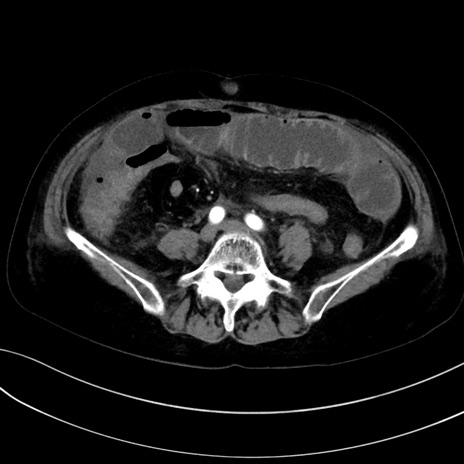

症例13 CT(横断像)1日半後